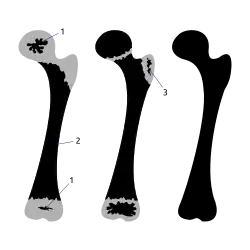

Апофизы окостеневают энхондрально из заложенных в их хряще центров окостенения и построены из губчатого вещества[1]. Так, например, у человека плечевая кость имеет три пункта окостенения в верхнем конце: эпифиз в головке и два апофиза в большом и малом буграх и четыре пункта в нижнем: два из них образуют эпифиз и два — апофизы, образующие внутренний и наружный мыщелки. Эти центры окостенения появляются на 3-м году жизни в большом бугре, на 5-м году — в малом и на 8-м — в обоих мыщелках. Объединение костной ткани апофизов с эпифизом происходит не одновременно: на 5-м году жизни присоединяется большой бугор, малый бугор сразу присоединяется сразу после образования, на 11-м году наружный мыщелок сливается с головчатым возвышением и на 18-м году к нижнему эпифизу прирастает внутренний мыщелок и в то же время нижний эпифиз сливается с телом кости ( верхний эпифиз прирастает на 20-м году жизни)[2].

Образование верхнего конца бедра происходит аналогично плечу. В нижнем конце на 4-м году возникает апофиз в большом вертеле и на 14—15-м году — в малом вертеле. Возникшие последними апофизы на нижнем конце бедра прирастают, наоборот, первыми на 17—18-м годах жизни человека[2].